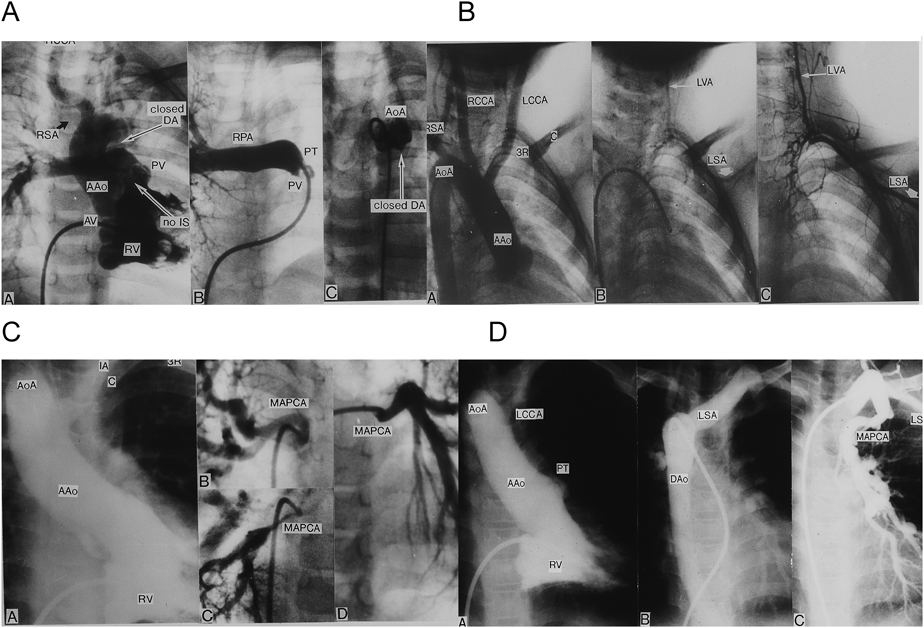

本症例では入院して造影検査などで心臓血管異常を詳しく調べると,非欠失例には少ない血管異常(Figs. 2, 3, 4)をしばしば合併することが明らかになった26–30)

Pediatric Cardiology and Cardiac Surgery 33(1): 3-9 (2017)

Fig. 2 Vascular anomalies associated with chromosome 22q11 deletion and tetralogy of Fallot (TF)

(A) TF, conus septal defect, aberrant right subclavian artery (RSA), and isolation of the left pulmonary artery (absent left pulmonary artery). (B) TF, pulmonary atresia (PA), right aortic arch (RAA), high aortic arch (HAA), and isolation of the left subclavian artery. (C) TF, PA, RAA, HAA, and the major aortopulmonary collateral artery (MAPCA). (D) TF, PA, MAPCA, and RAA. Aberrant left subclavian artery (LSA). AAo: ascending aorta, AoA: aortic arch, AV: aortic valve, DA: ductus arteriosus, DAo: descending aorta, F: frontal, IA: innominate artery, IS: infundibular septum, L: lateral, LCA: left coronary artery, LCCA: left common carotid artery, LPA: left pulmonary artery, LSA: left subclavian artery, LVA: left vertebral artery, MPA: main pulmonary artery, PT: pulmonary trunk, PV: pulmonary valve, RCCA: right common carotid artery, RPA: right pulmonary artery, RSA: right subclavian artery, RV: right ventricle, 3R: 3rd rib. Modified and cited with the permission of the authors and publisher from references 26) and 27).

22q11欠失症のFallot四徴症では右側大動脈弓,鎖骨下動脈レベルに達する高い大動脈弓,鎖骨下動脈起始異常,漏斗部心室中隔全欠損の合併がdel22欠失を合併しないFallot四徴症より多い26, 27).欠失症例での頻度と非欠失例での頻度が次のように報告20)されている.すなわち,右側大動脈弓(70% vs 23%)(欠失例での% vs非欠失例での%),高い鎖骨に届く大動脈弓(50% vs 10%),動脈管欠損+MAPCA(91% vs 50%)などである.漏斗部中隔全欠損のFallot四徴症(Fig. 2A)は欠失症Fallot四徴症では30%,非欠失症Fallot四徴症では5%である.したがってFallot四徴症症例にこれら稀な異常を合併したときには染色体22q11欠失の検索をすべきである31).本症候群のFallot四徴症+肺動脈閉鎖(Fallot四徴症極型)では動脈管開存を合併する例は少なく,大部分がMAPCAを合併する27)